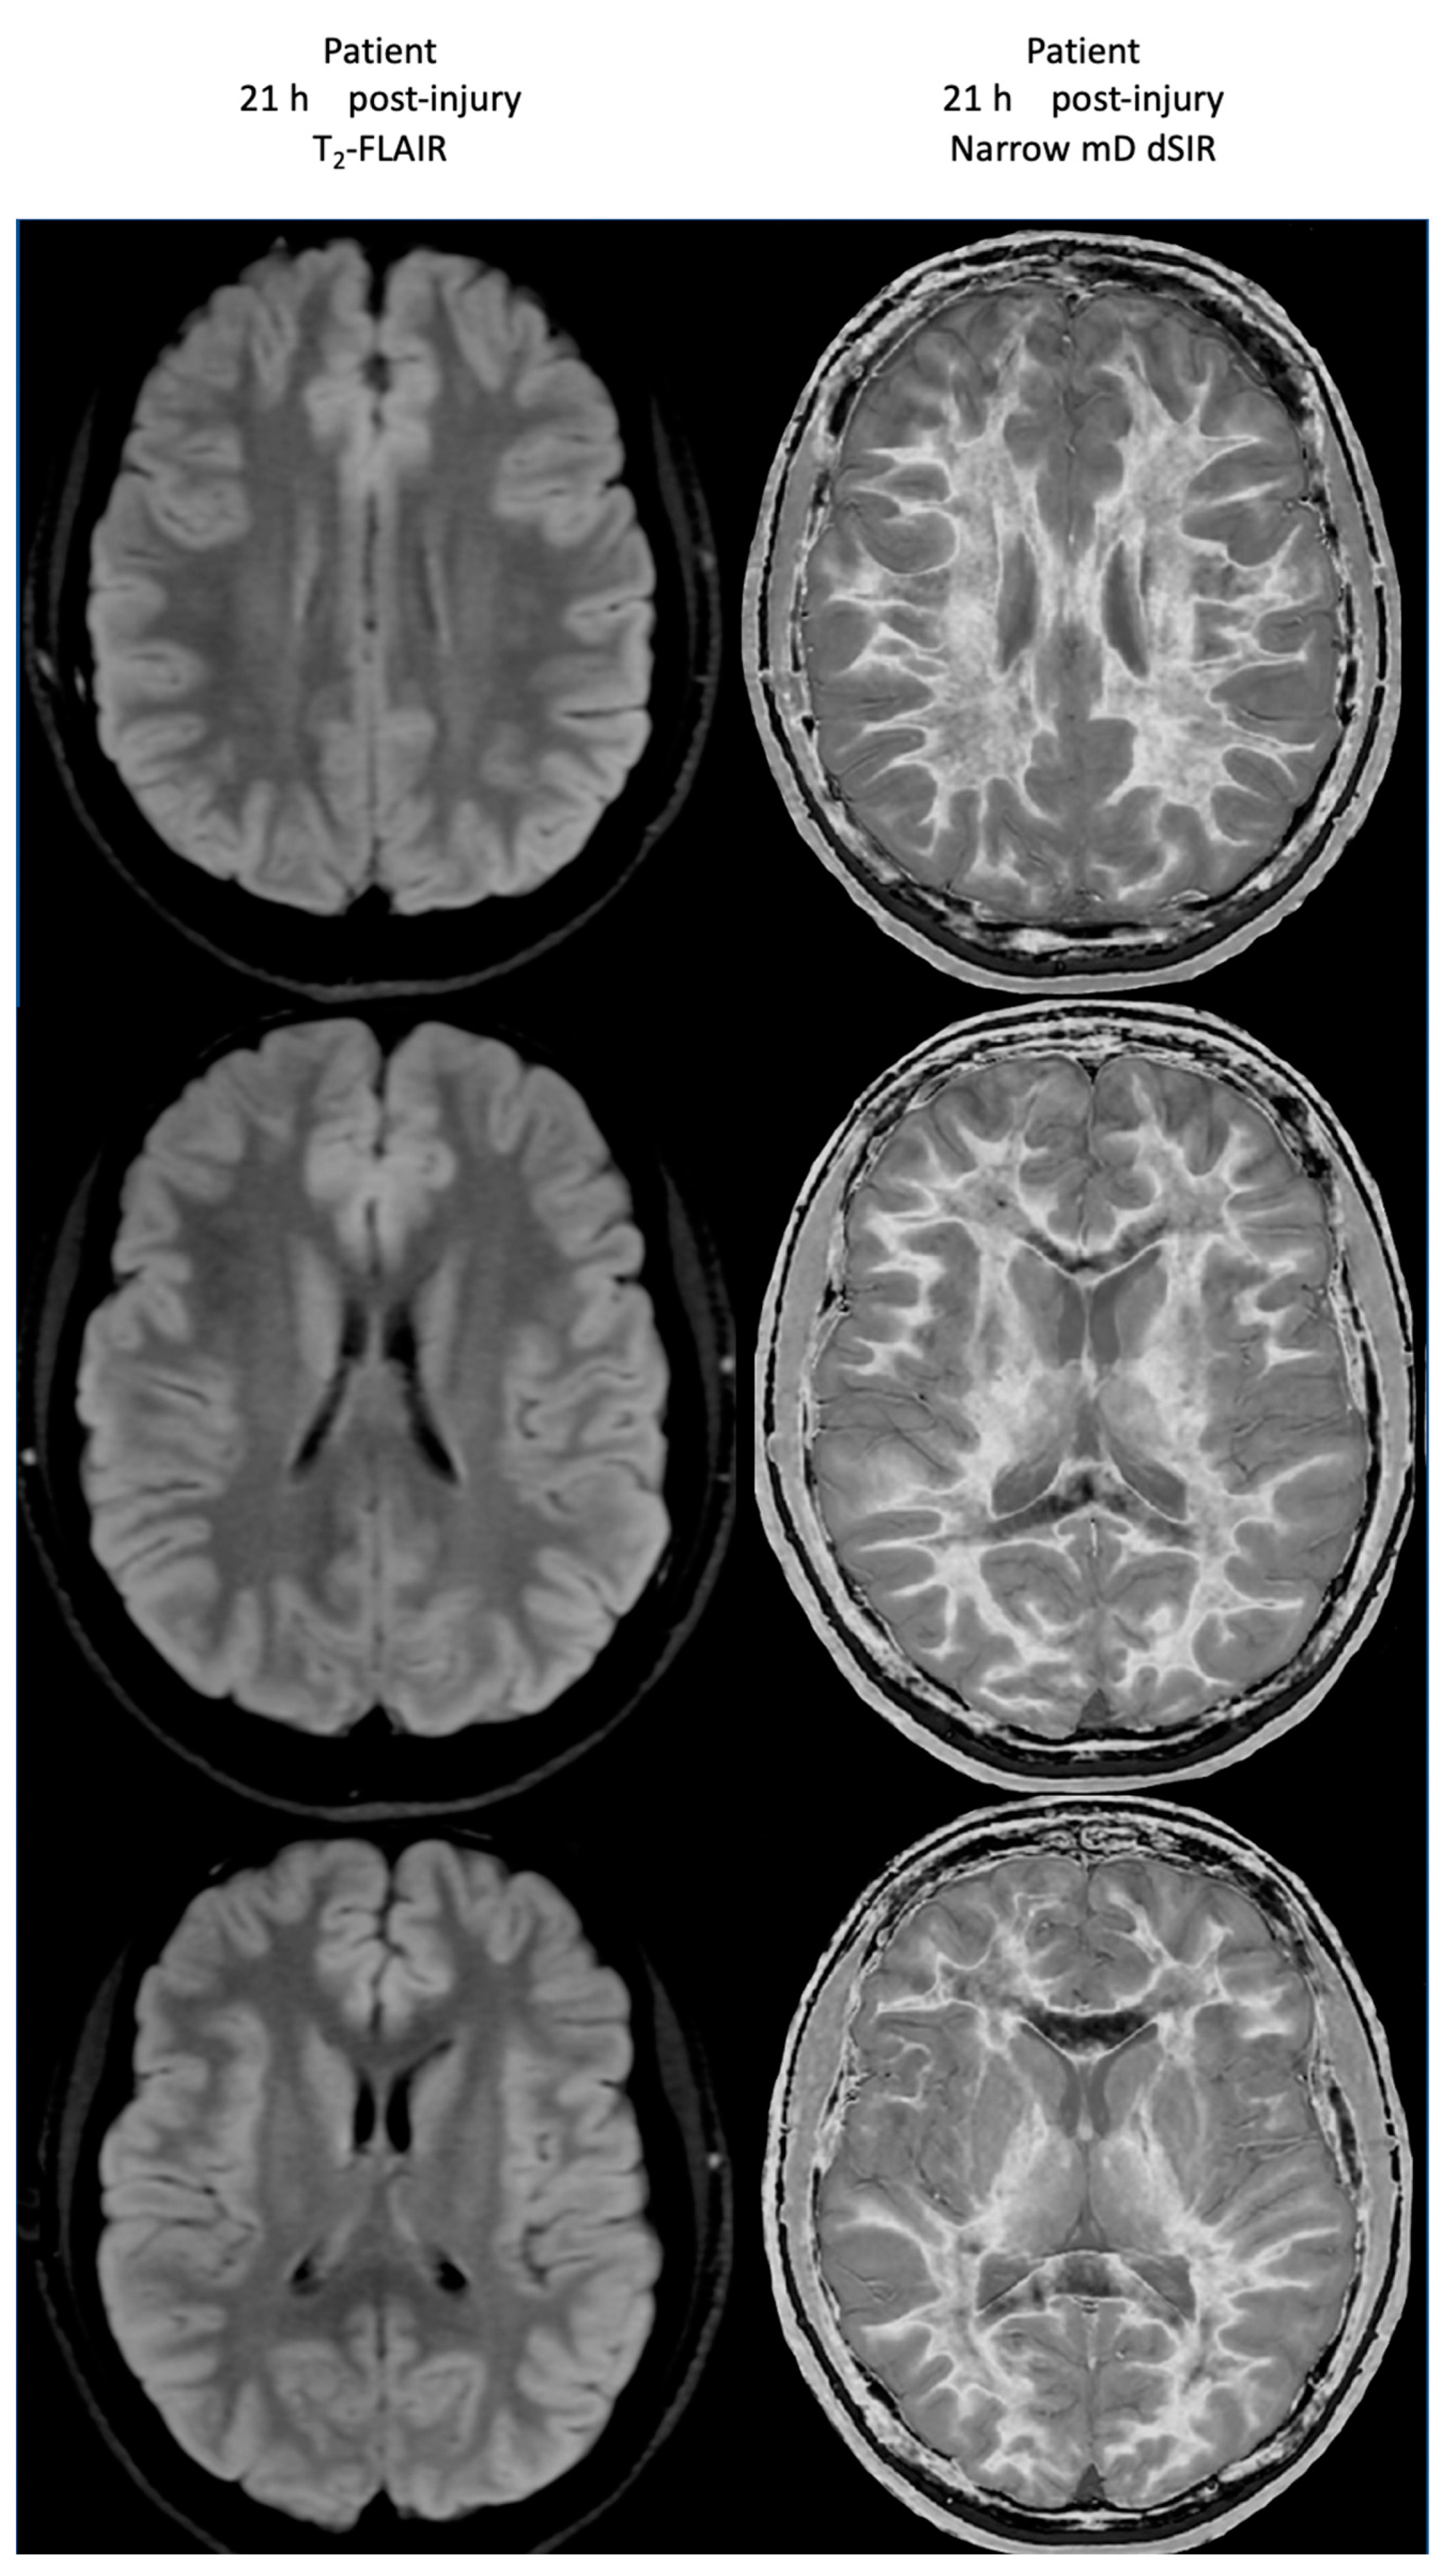

At his first examination 21 h post-injury, his T2-FLAIR images were normal (Figure 20, left column) but his narrow mD dSIR images (right column) showed extensive high signal abnormalities in the white matter of his cerebral hemispheres with sparing of the anterior and posterior corpus callosum, as well as some sparing of the peripheral white matter in the cerebral hemispheres, consistent with a whiteout sign grade 4. This is quite different from the low signal seen in the white matter of the age matched normal control dSIR image shown in Figure 16, which is whiteout sign grade 1.

Figure 20.

Case 2 Acute mTBI imaged at 21 h post-injury. T2-FLAIR (left column) and narrow mD dSIR (right column) images. No abnormality is seen on the T2-FLAIR images. On the dSIR images, extensive high signal abnormalities are seen in most of the white matter with sparing of the anterior and posterior central corpus callosum and posterior white matter of the cerebral hemispheres. The appearances are consistent with a whiteout sign grade 4.